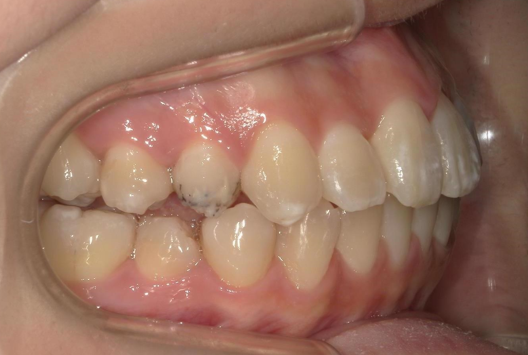

年齢 20代女性

主訴

上顎前突

前歯叢生

治療期間 2024年3月~25年12月

矯正種類 マウスピース矯正(クリアコレクト)

BEFORE